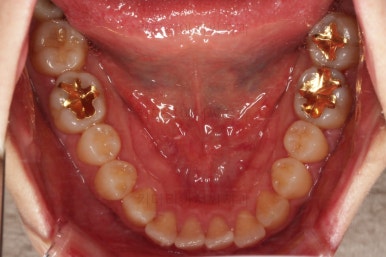

초진 시, 입안의 모습이에요.

결손부위가 눈에 띄고요.

결손부위가 양쪽에 있다보니 윗니 중간에 틈새가 벌어졌네요.

뒤쪽의 빈공간으로 치아들이 도미노처럼 쓰러져서 그렇습니다.

앞니의 약간의 틈새, 약간의 삐뚤어짐, 약간의 중앙선 틀어짐 등 심하진 않으나 약간씩의 문제점들이 있네요.